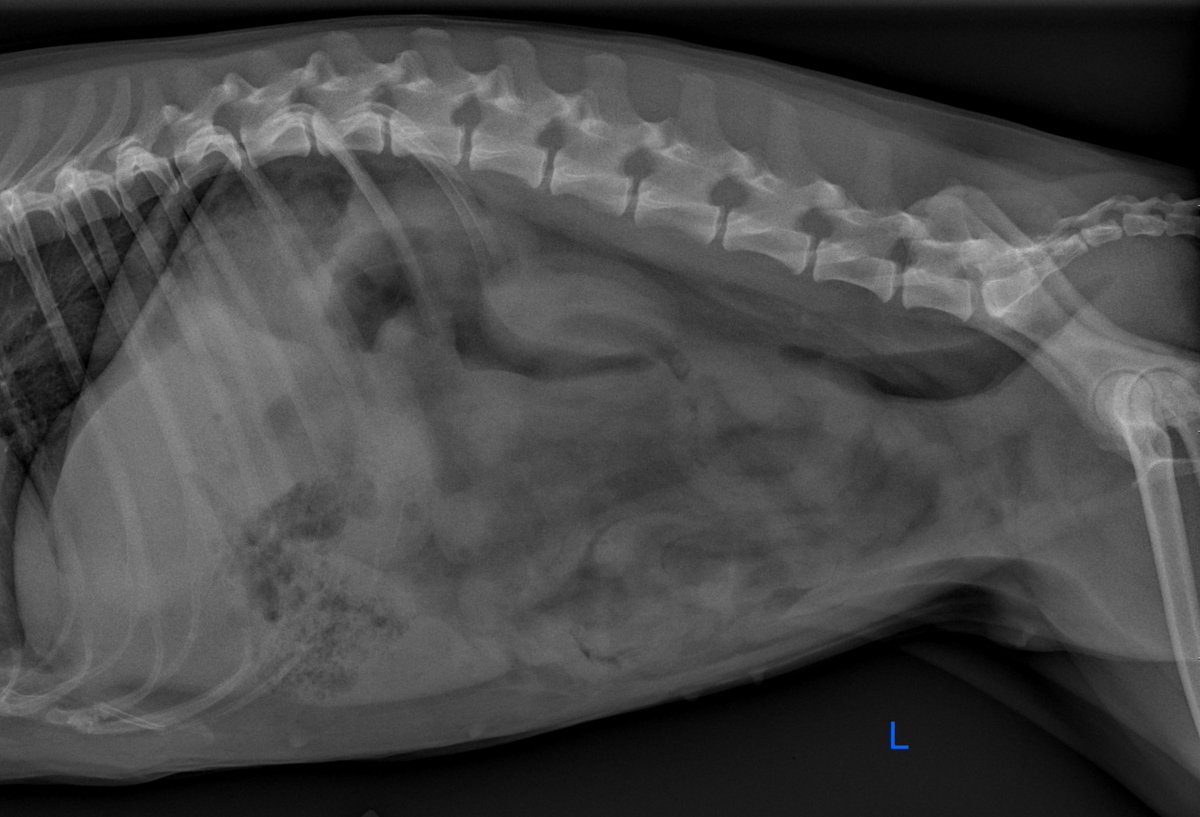

- School Ager With A Catheter That Does Not Infuse Pediatric Radiology Case Pediatricimaging Org Pedsimaging , Radiology Department Of The University Medical Centre Of Utrecht And The Interactive Digital Education (Part I), F.j.a.

- Info Vet Ct Com On Twitter It S Your Case Day 5 8 Yo Old Eng Sheepdog Vomiting And Anorexia For 3 Days Read The Full Case Here Https T Co Aqu7Ptkbxl Vetstudent Radiology Casestudy Mondaymotivaton Https T Co Sp3Eknj8Si , Notice That The Periostitis Is Aggressive, But Not As Aggressive As In The Other Two Cases.

Browse our spinal case study library where spine specialists present many cases that are challenging and compelling. The two main forms of ossification occur in different bones, intramembranous (eg skull) and endochondral. Learn vocabulary, terms and more with flashcards, games and other study tools. Erik beek and robin smithuis. Beek, radiologist, radiology department of the wilhelmina. Learn what you might experience, how to prepare for the exam, benefits, risks and skeletal scintigraphy helps to diagnose and evaluate a variety of bone diseases and conditions using small amounts of radioactive materials called. Treatment with radical resection of the proximal 1/2 of the femur and prosthetic reconstruction | pdf version. From a study of the age prevalence of 4,000 malignant bone tumors, he gives the following table keep in mind that the classic descriptions of bone tumors that you spend so much time studying are for untreated lesions. The time of the procedure, and be. Published bypolly gaines modified over 3 years ago. It requires an injection of a small amount of radioactive fluid all films are returned to the radiology department at the nuffield orthopaedic centre for reporting. The most common sesamoid bones are those of the foot, including the hallucal sesamoids, lesser metatarsal sesamoids, interphalangeal joint sesamoid of the great toe, os. Mri examination of the ankle. Bone lesions are commonly encountered in pediatric patients, with primary bone tumors representing the 6th most common neoplasm. Studies show that patients with low levels of vitamin d have lower bone density or bone mass and are more likely to break bones when they are older. Each case provides a patient's history, exam and imaging, treatment, outcome and peer discussion. Many prenatal bones fuse postnatal developing neonate and child (about 275). Bone densitometry differs from diagnostic radiology in that good image quality, which can tolerate variability in technique, is not the ultimate goal. Savesave case study bone for later. Start studying bone case studies. Bone archives chest cases of the week. I would summarize this book as a radiologists perspective on skeletal structure, function, pathologies starting with bone, and. Age assessment by ultrasonography are needed. 3 or more views 1 ac joints 1 ankle 3 views 1 bone age studies 1 chest single view 1 chest 2 views 1 chest 3 views 1 chest 4 or more in which case, the metformin should be temporarily discontinued at. Browse our spinal case study library where spine specialists present many cases that are challenging and compelling. Radiology department of the university medical centre of utrecht and the interactive digital education (part i), f.j.a. Please allow two weeks for the results to be sent to. Has been added to your cart. It is based on radiology assistant website. 0 ratings0% found this document useful (0 votes). Suei et al studied the relationship between the radiographic findings and treatment outcome (healing or.